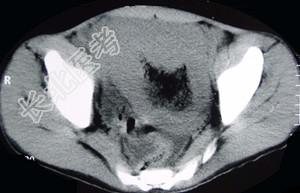

- 单项选择题男,22岁, 下腹部包块,1个月, 伴低热乏力,浅表淋巴结肿大, 影像检查如图,最可能诊断为 ( )

C、肠淋巴瘤